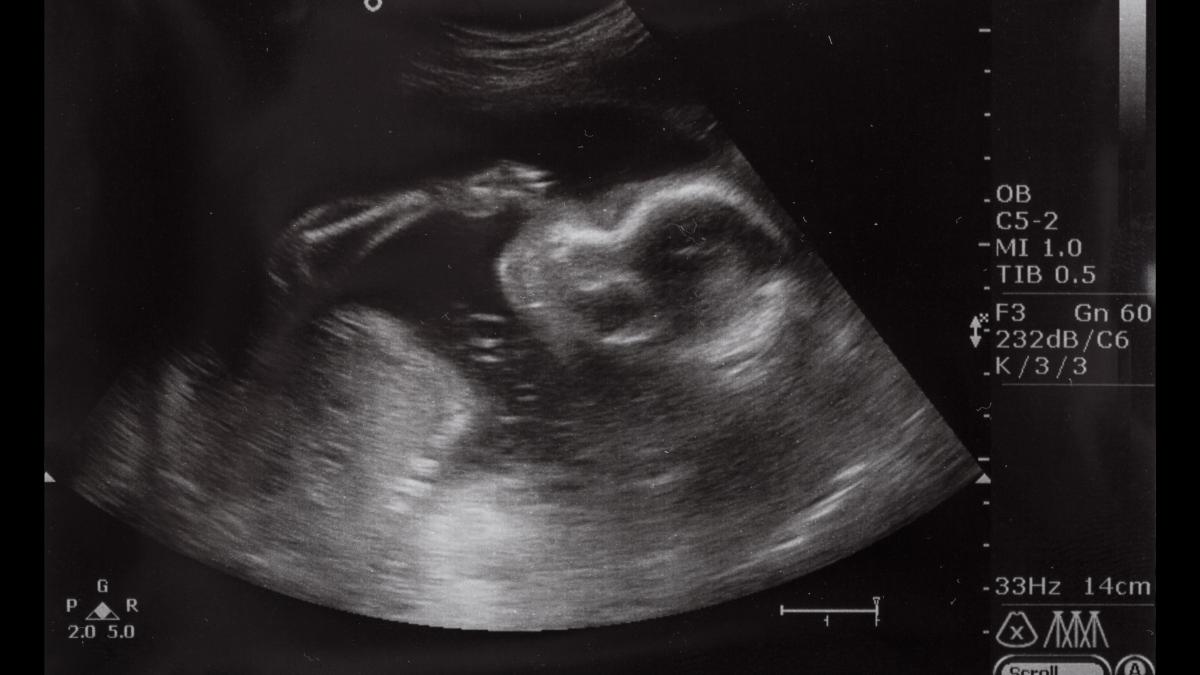

Imaginea unui bebeluș afectat, vizibil chiar la ecografie, ar trebui să fie un avertisment clar pentru toți că aceste riscuri nu trebuie subestimate.

SURSA FOTO: captură abc.es/familia